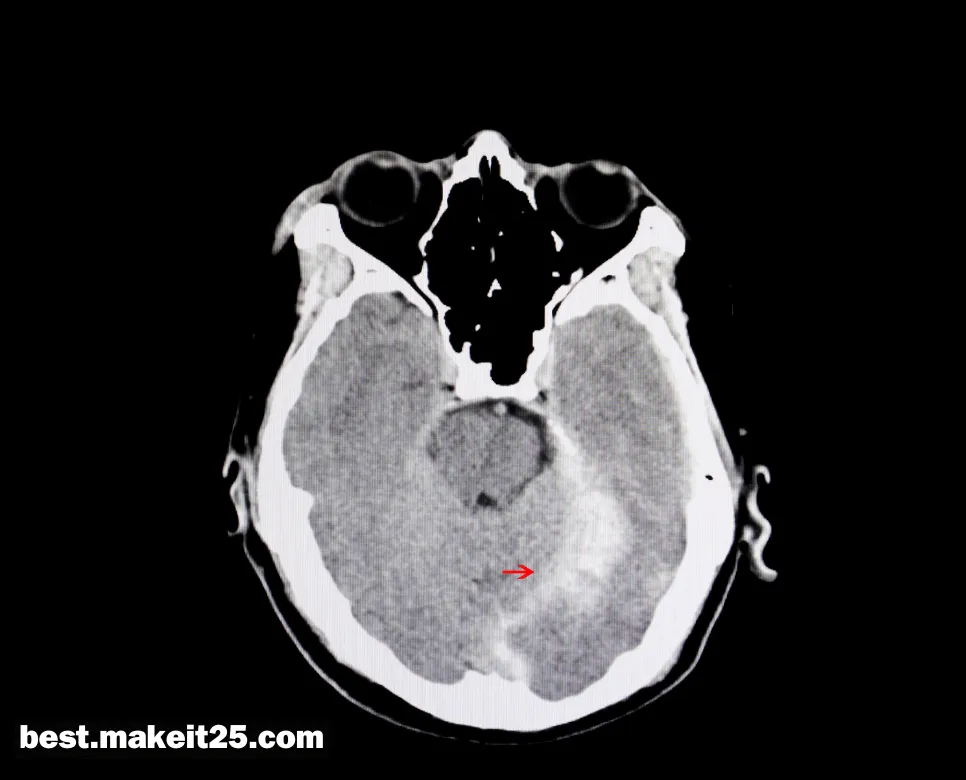

ICH(뇌내출혈)

ICH는 의학 용어로 Intracerebral Hemorrhage의 약자이며, 한글로는 ‘뇌내출혈’을 의미합니다. 뇌내출혈은 뇌 실질 내에 위치한 혈관이 파열되어 발생하는 비외상성 출혈로, 뇌졸중의 한 유형입니다. 고혈압, 뇌동맥류, 뇌혈관기형 등이 주요 원인이며, 두통, 의식 변화, 신경학적 결손 등의 증상이 나타날 수 있습니다.

뇌내출혈의 진단과 치료

- 영상 검사: CT나 MRI를 통해 뇌내출혈의 위치와 크기를 확인하고, 원인 질환을 감별합니다.

요약하면, ICH는 주로 뇌내출혈을 의미하는 의학 용어로, 뇌 실질 내 혈관의 파열로 인해 발생하는 비외상성 출혈입니다. 고혈압, 뇌동맥류, 뇌혈관기형 등이 주요 원인이며, 두통, 의식 변화, 신경학적 결손 등의 증상을 나타냅니다. CT, MRI 등의 영상 검사와 신경학적 검진을 통해 진단하고, 약물 치료와 수술적 치료를 병행하여 관리합니다. 또한, ICH는 면역조직화학염색법과 국제조화회의를 의미하기도 합니다.